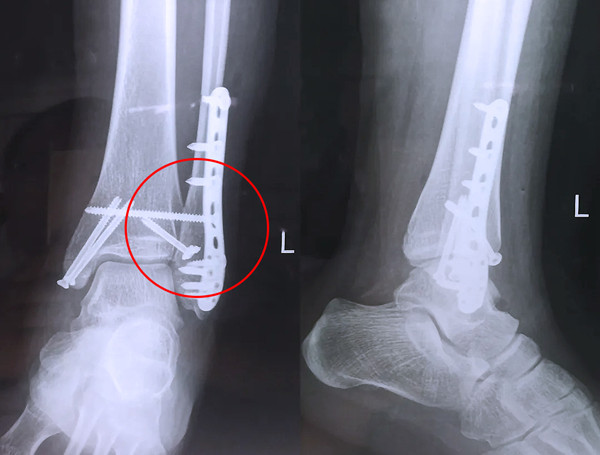

踝關節(jié)骨折在X影像上的表現(xiàn)有很多種。如內踝骨折和外踝骨折,我們可以在影像上看到骨折處的骨折線是不連續(xù)的。還有后踝的骨折,內踝、外踝、后踝聯(lián)合在一起發(fā)生的骨折,我們稱之為“三踝骨折”,這些都是在X影像上能夠顯示出來的。

內踝骨折

外踝骨折

后踝骨折

三踝骨折